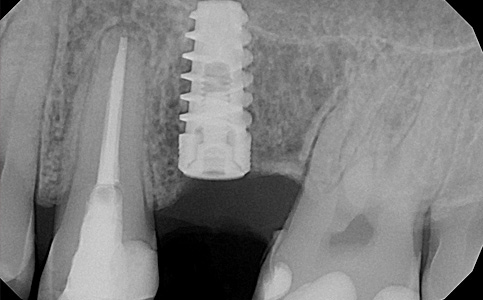

Przykład uzupełnienia pojedynczego braku zęba implantem. Implant imituje korzeń zęba, który w połączeniu z koroną protetyczną tworzy pełnowartościowy ząb.